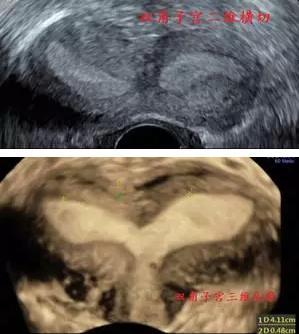

马蹄形子宫

8种常见子宫畸形声像图!